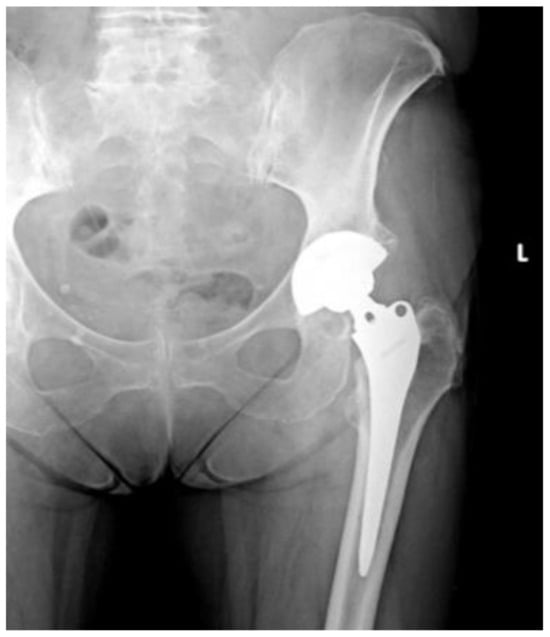

Of the 84 patients enrolled in this study, 44 patients (52.4%) received a THA with a straight stem (group A) (Figure 1 and Figure 2) and 40 patients (47.6%) received a THA with an anatomical stem (group B) (Figure 3 and Figure 4).

Figure 4.

Axial X-rays view of a total hip arthroplasty with anatomical stem (group B).